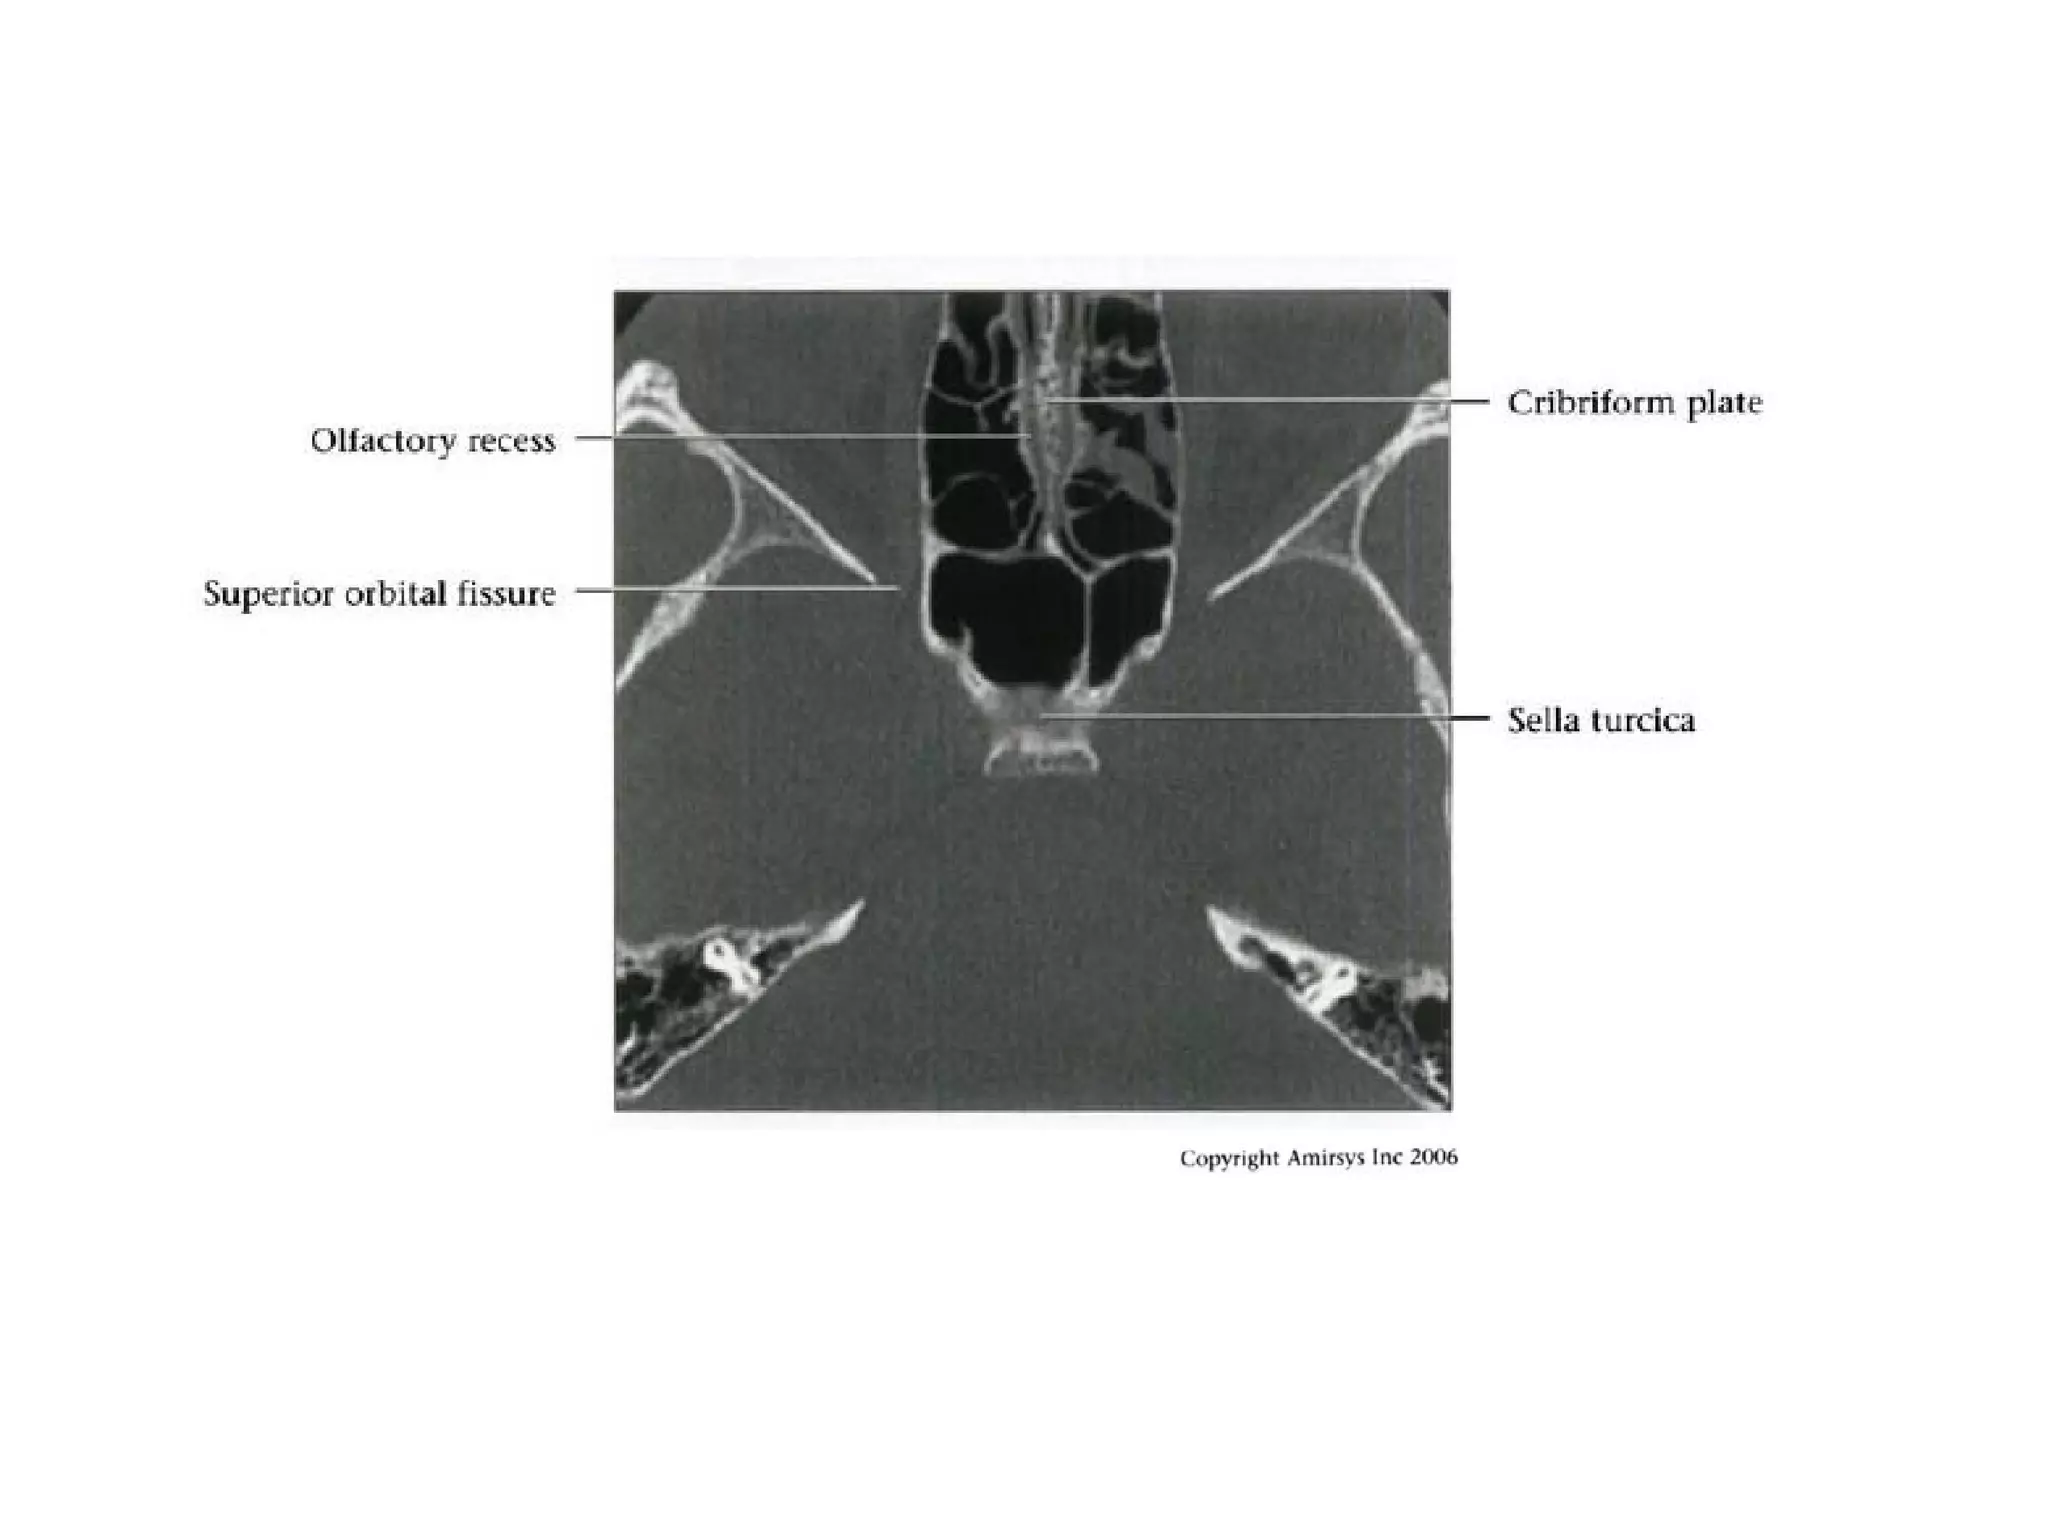

Clinoid (C5) segment

• Between proximal, distal dural rings of

cavernous sinus

• Ends as ICA enters subarachnoid space

near anterior clinoid process

• No important branches unless ophthalmic

arteries arises within C5

Ophthalmic (C6) segment

• Extends from distal dural ring at superior clinoid

to just below posterior communicating artery

(PCoA) origin

• Two important branches

- Ophthalmic Arteries (originates from

anterosuperior ICA, passes through optic canal

to orbit; gives off ocular, lacrimal, muscular

branches; extensive anastomoses with ECA)

- Superior hypophyseal artery (courses

posteromedially; supplies anterior pituitary,

infundibulum, optic nerve / chiasm)